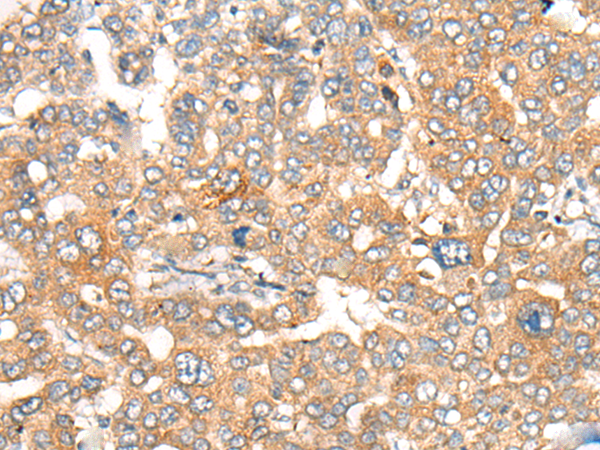

IHC positive control: |

Human liver cancer and human cervical cancer |